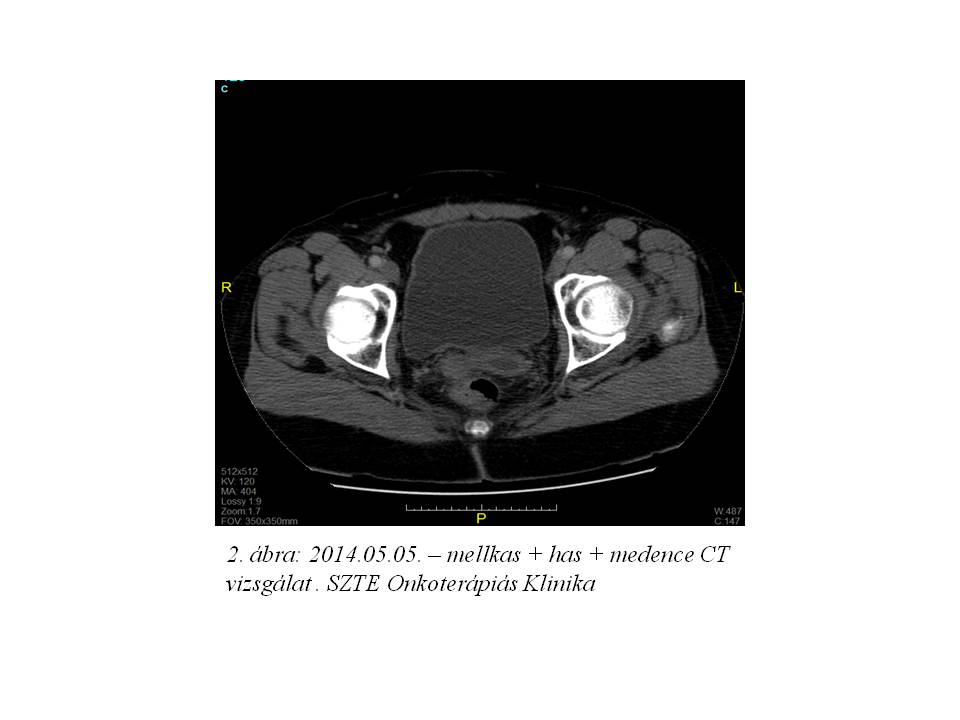

2014. márciusban a beteg rendellenes hüvelyi vérzés miatt jelentkezett nőgyógyászati kontrollon. Fizikális vizsgálattal egyértelműen recidíva nem igazolódott. Has + kismedencei CT vizsgálat történt, mely multiplex hepaticus metastasisokat, valamint jobb oldali pyelectasia mellett a hólyag és a rectum közötti régióban kismedencei recidíva radiológiai képét, és a jobb tüdőbázison is bizonytalan gócot írt le. (1. ábra, 2. ábra, 3. ábra, 4. ábra).